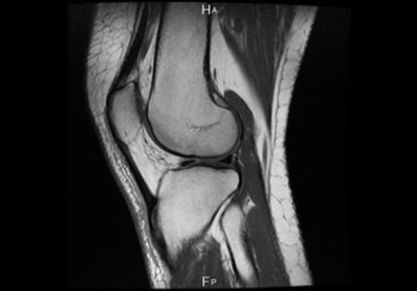

МРТ суставов

МРТ суставов — один из самых передовых и информативных методов исследования в современной медицине. Данный вид диагностики позволяет обнаружить аномалии развития и патологии тканевых структур в суставах, тщательно изучить близлежащие кровеносные сосуды и нервные окончания. Обследование основано на применении безопасного для здоровья человека магнитного излучения, поэтому при необходимости может проводиться даже беременным женщинам во 2